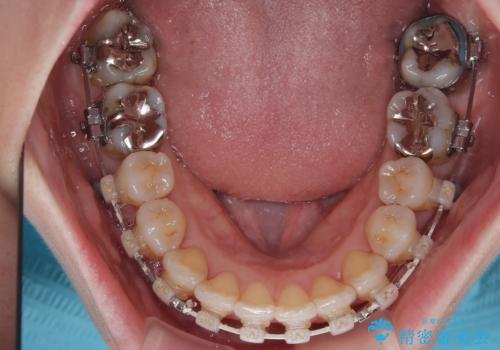

- 矯正装置

- 審美装置

- 前歯のデコボコや、やや突出した感じを気にして来院された患者様です。

抜歯矯正を必要とするほど口元の突出感はなく、本人もそこまでは気にしていない様子でした。

お仕事柄、マウスピース装着は困難とのことで、表側のワイヤー矯正にて治療を行うこととしました。

デコボコ解消の際に、前歯が前突するリスクがあったため、舌突出癖の改善と、アンカースクリューによる加強固定を行うこととしました。

矯正治療後には奥歯の銀歯やむし歯をセラミックやゴールドにて治療を行い、大変整った口腔環境へと改善さ。れました